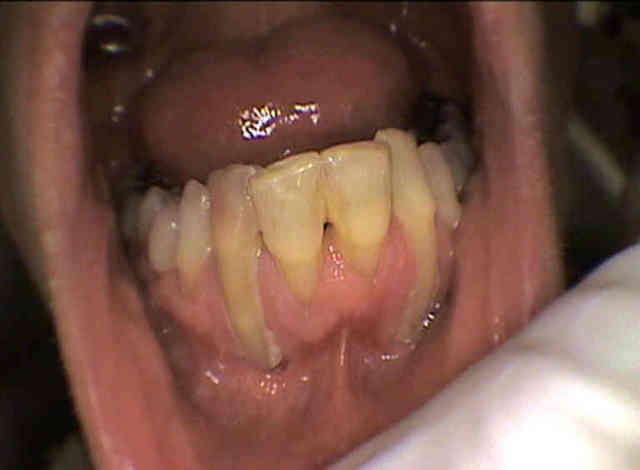

27/06/2008 à 16h35

Vanpire inversé : qui veut faire un recouvrement?